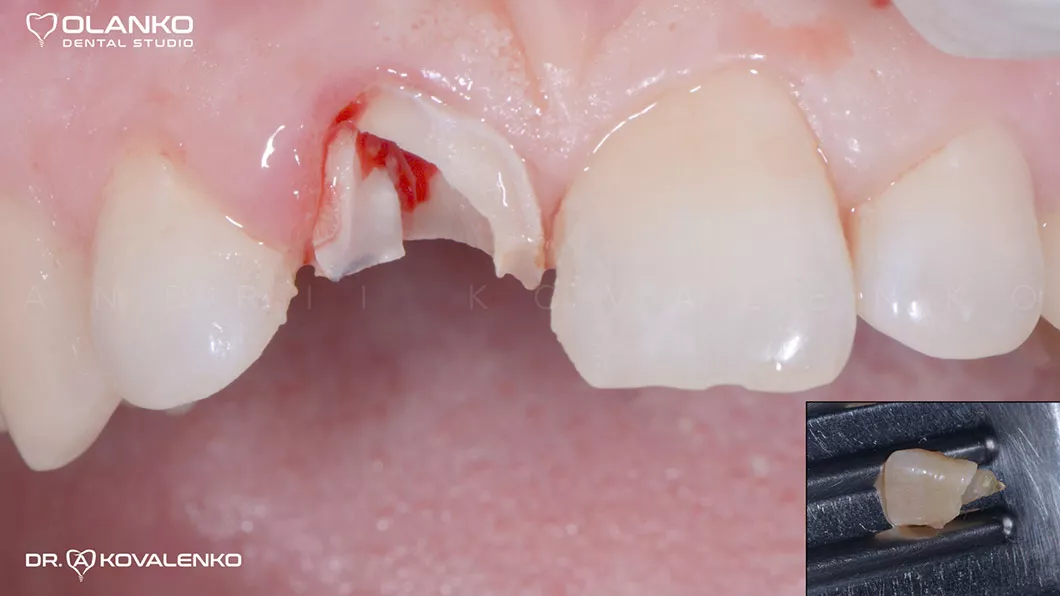

Пациентка обратилась с травмой переднего верхнего резца (отлом коронковой части и трещина корня).

Проведено

Лечение: удаление корня с одномоментной имплантацией в лунку удалённого зуба, и изготовлением временной коронки на имплантате.

Ситуация до

Клинический случай 5 имплантация зубов